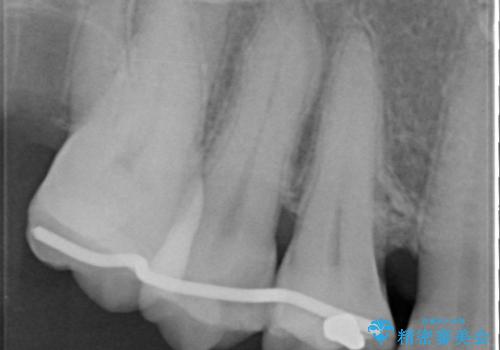

部分矯正を含む 歯周病治療 (再生治療・歯周ポケット除去・MTM・連結補綴)

検査の結果、強い歯ぎしりによる歯の周囲の骨の吸収が認められたため歯槽骨の再生・歯周ポケットの除去・力に対抗する連結補綴・補綴前処置としての小矯正を計画します。

特定の歯に強く力がかかりまた歯周病により臨床歯根が短くなっているような場合、歯の動揺を抑えるため連結補綴が検討されます。

歯の動揺が続くとより周囲の骨を失い最終的には歯を喪失してしまう可能性が高くなってしまうためです。

今回連結補綴を行うにあたり、歯周病の問題を解決するために再生療法・歯周ポケット除去手術を、またより歯の神経を保存し力に対抗できる環境を整えるために小矯正を行い精度の高いメタルボンドクラウンを製作することができました。